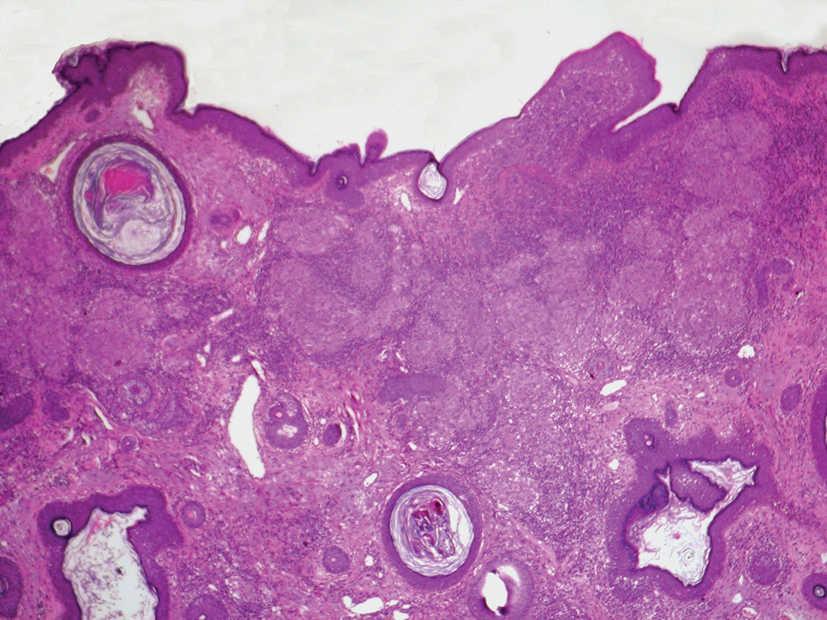

Se realizó una biopsia de la lesión facial y del borde activo de la placa del antebrazo. El estudio histológico mostró, bajo una epidermis respetada, un infiltrado granulomatoso dérmico (fig. 3). Los granulomas eran de tipo tuberculoide, aunque sin necrosis caseosa central. Estos granulomas eran confluentes, formados por histiocitos, algunos de aspecto espumoso y escasas células de Langhans. En la periferia de los granulomas se observaban abundantes linfocitos (fig. 4). En la tinción con de Ziehl-Neelsen no se detectaron bacilos ácido-alcohol resistentes.

Fig. 3.--Granulomas tuberculoides, con abundantes linfocitos en la periferia de los mismos. (Hematoxilina-eosina, x10.)